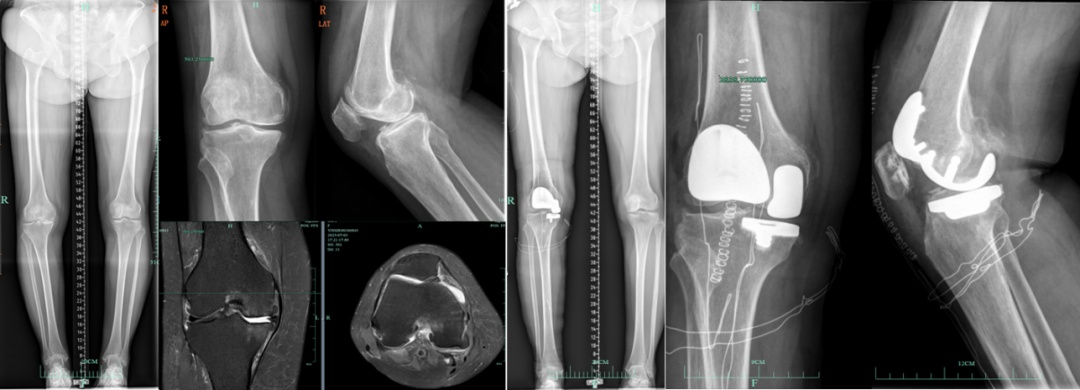

适用于同时存在内侧间室与髌股关节严重磨损,但外侧间室及膝关节关键韧带(如前交叉韧带)功能完好的患者。通过一次手术、一个切口,精准置换内侧间室和髌股关节,完整保留健康的外侧间室以及膝关节所有的原生韧带与运动机制。

相较于传统的全膝关节置换,它实现了“2/3个膝关节的微创置换”,保留了患者自身关节超过三分之一的原生结构。核心优势在于最大程度上避免全膝置换,既能同时解决行走负重痛和膝前活动痛,又保有了部分天然关节的感觉与功能,具有创伤小、出血少、康复快、本体感觉保留佳的优势。